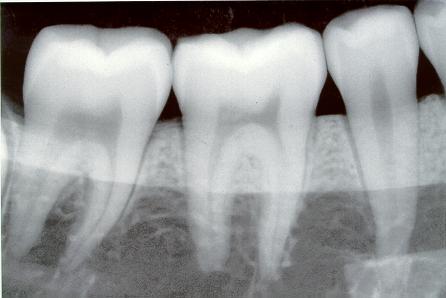

Radiografías dentales se relacionan a meningiomas

¿Qué debe hacer la próxima vez cuando el dentista le diga que debe tomarse una radiografía dental completa? Un nuevo estudio demuestra que debe limitar la cantidad de exposición a la radiación en el transcurso de la...